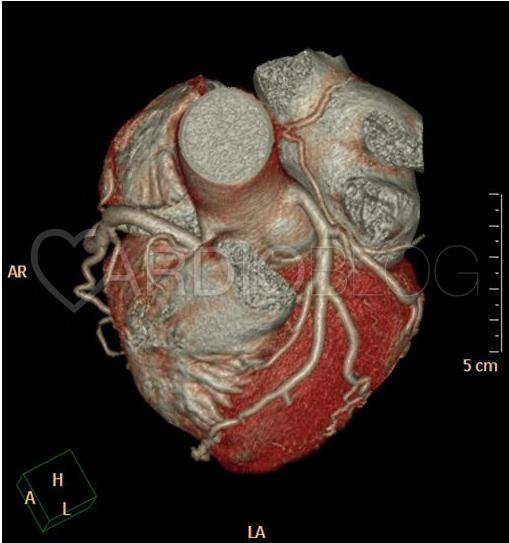

A 3D rekonstrukció, amely jobb domináns, szabályos eredésű és lefutású coronaria rendszert mutat. A képminőség kiváló, érdemi mozgási műtermék nem látható